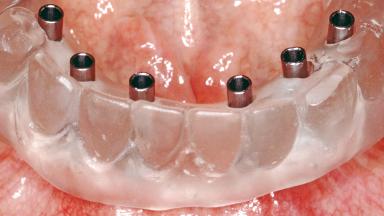

Conventional Loading of Six Implants in the Mandible and Final Restoration with a Full-Arch Metal-Ceramic FDP

A 68-year-old, completely edentulous male patient presented for evaluation and treatment options. He reported excellent general health and was taking no regular medication. He had been edentulous for approximately 12 years, having lost his teeth to periodontal disease and dental caries. The patient’s chief complaint was incompetent function. His secondary concerns included his appearance and the desire for a predictable outcome. He attributed his reduced functional capacity to his lower complete denture, which he described as poor. He was particularly concerned with the denture’s instability and poor fit. In general terms, he was satisfied with the maxillary complete prosthesis. The maxillary prosthesis was characterized by adequate retention, stability, and support, although the fit was considered less than ideal.

# of Implants 6

Type of Implants One-Piece

Attachment One-Piece